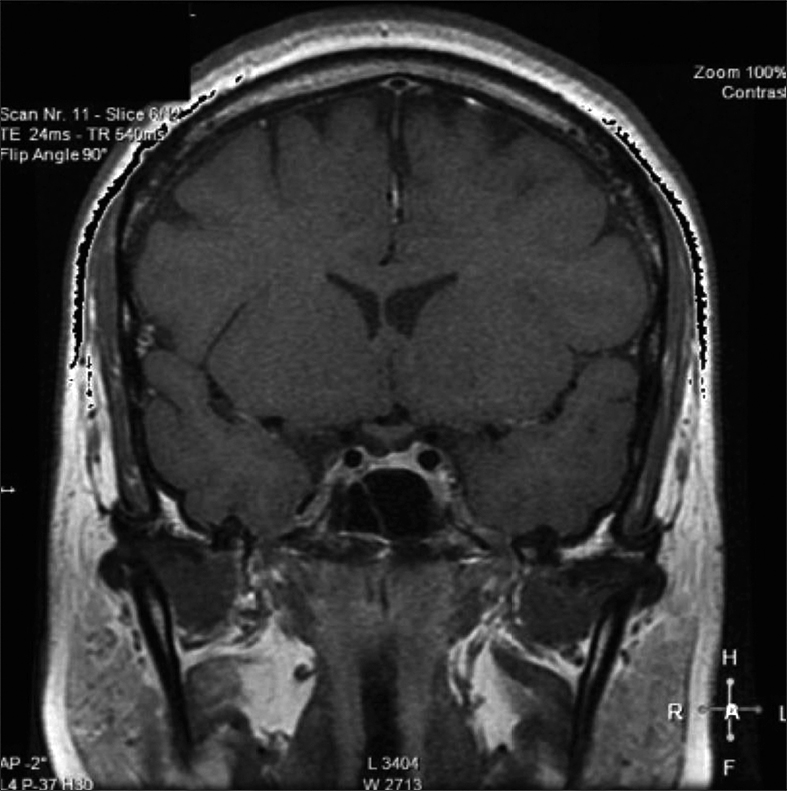

Posteriormente, consultó con especialista endocrinólogo donde se le solicitó exámenes que destacaba: glicemia 97 mg/dl, creatininemia 0,71 mg/dl, sodio 145 mEq/l, potasio 3,6 mEq/l, cloro 105 mEq/l, FSH 3,8 MUI/ml, Estradiol 12 pg/ml, prolactina 20,6 ng/ml, TSH 4,69 UI/ml, T4 libre 1,0 ng/dl, IGF-1 30,8 ng/ml (130-354), cortisol 151 ng/ml (40-230). Resonancia magnética (RM) de la región selar informó “silla turca normal, engrosamiento nodular del tercio medio distal del tallo hipofisiario y no se identifica señal de la neurohipófisis” (Figura 1). Se ajustó DDAVP a 2 puff en la mañana y 1 puff en la tarde, logrando ya normalizar la diuresis diurna y no tener nicturia. Se solicitó control RM en forma precoz para evaluar evolución de engrosamiento del tallo y segunda resonancia informó “no se identifica señal de neurohipófisis, evolución regresiva del engrosamiento del tallo hipofisiario respecto a RM previa” (Figura 2). Se establece diagnóstico de Infundibuloneurohipofisitis, Diabetes Insípida central y amenorrea secundaria por hipogonadismo hipogonadotrópico. La paciente evoluciona en forma adecuada, asintomática, con completo control de la diuresis, y dado el compromiso gonadal y la edad se inició terapia reemplazo hormonal. Siguiente RM evidenció normalización del grosor del tallo hipofisiario, sin evidenciar la neurohipófisis.

Figura 1. Engrosamiento nodular del tercio medio distal del tallo hipofisiario.

Dentro del correcto diagnóstico de la INH está la neuroimagen, donde la RM es el método de elección. Los hallazgos comúnmente encontrados son el engrosamiento del infundíbulo y del tallo hipofisiario (se considera engrosamiento si es mayor a 4 mm) y la pérdida de señal de la neurohipófisis (hay que considerar que el 10% de la población normal no la presenta, especialmente en ancianos). Esta asociación, ausencia de señal de neurohipófisis y engrosamiento del tallo hipofisiario, son altamente sugerentes de INH. En nuestra paciente se encontraron ambos fenómenos, y considerando la regresión del engrosamiento del tallo hipofisiario lo hacía compatible con INH. La adenohipófisis en la RM es usualmente normal en tamaño e intesidad a la señal. Siendo el engrosamiento del tallo hipofisiario el hallazgo cardinal a la imagenología, inicialmente se le denominaba “Stalkitis” a esta entidad10; sin embargo, la denominación INH es la más idónea debido a que anatomopatológicamente el compromiso es del infundíbulo, tallo y neurohipófisis. Respecto al engrosamiento del tallo hipofisiario en muy importante considerar su diagnóstico diferencial9. Una adecuada historia clínica, manifestaciones clínicas, imagenología y en ocasiones biopsia darán el diagnóstico adecuado. En la Tabla 1 se enumeran las etiologías de engrosamientos del tallo hipofisiario aisladas.